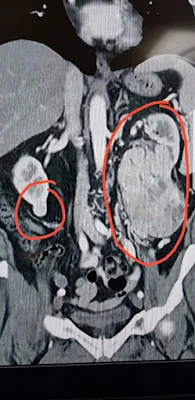

MÉRIDA, Yucatán.- El tumor renal es un área anormal dentro del riñón, y algunas personas pueden presentar tumores benignos (no cancerosos) o malignos (cancerosos), y la técnica más eficaz para el tratamiento de estos pacientes es la nefrectomía por laparoscópica, misma que actualmente se realiza en el Instituto Mexicano del Seguro Social (IMSS) en Yucatán, informó el Urólogo Moisés Hernández Hernández.

La mayoría de los pacientes diagnosticados con tumor renal puedan ser tratados mediante una nefrectomía laparoscópica, principalmente los que presentan tamaños menores de 4cm. Aun así, los tumores de mayor tamaño también pueden ser tratados mediante esta técnica, dependiendo de los casos.

Sin embargo, fue intervenido en el Seguro Social en un solo tiempo quirúrgico con duración de tres horas de quirófano, siendo dado de alta a las 48 horas posteriores. Los doctores lograron preservar el riñón derecho y el paciente no tuvo que recurrir a la hemodiálisis, a otro seguimiento médico y tampoco presentó secuelas.

“Estoy vivo, la operación fue gratuita y realmente me siento bien. Ahora cuido más mi salud, pero sé que soy afortunado, pues me detectaron a tiempo lo que tenía y aunque esperé con paciencia, los doctores me programaron para cirugía, me quitaron los dos tumores que tenía y salvaron mi vida”.